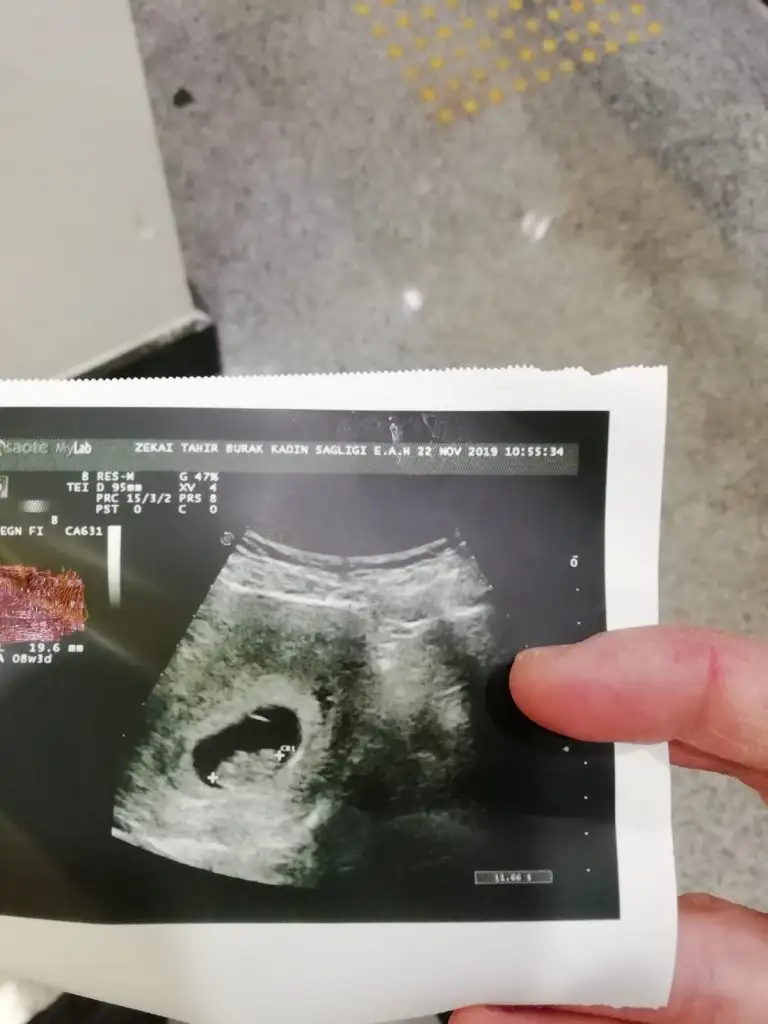

Yolk sac solda karından bakıldıysa yolk saca tutunuyor bebek buna göre erkekEki Görüntüle 2576955 5+2 sadece kese var bebek görünmüyor keseye göre var mı bi tahmini olan?

Evet karından bakıldı teşekkür ederimYolk sac solda karından bakıldıysa yolk saca tutunuyor bebek buna göre erkek

Yinede siz 11 yada 11 hafta nub için paylaşınEvet karından bakıldı teşekkür ederim